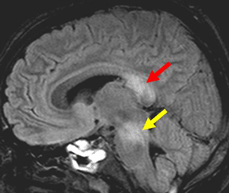

DAI, because traumatic lesions associated with DAI are often located centrally in the brain. Although disadvantages of FLAIR include a long examination time and the fact that it yields fewer slices ... Document Viewer

Magnetic Resonance Imaging Of Diffuse Axonal Injury ...

Diffuse axonal injury (DAI) is a common mechanism of traumatic brain injury (TBI) for which there is no well-accepted anatomic measures of injury severity. ation of brain lesions by suppressing the effect of cere-brospinal fluid (CSF), ... Access Content